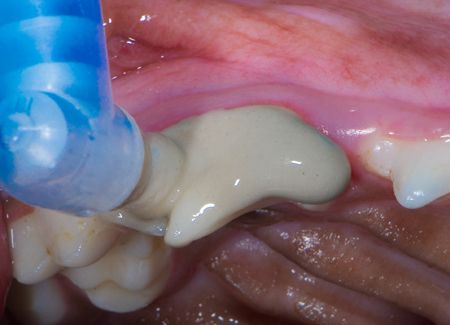

Once plaque, calculus and gingivitis are apparent, dental scaling, irrigation and polishing are indicated for treatment. Application of dental sealants and home care including the daily use of VOHC-accepted products help to reverse the gingival inflammation.

Then the teeth were polished with pumice.